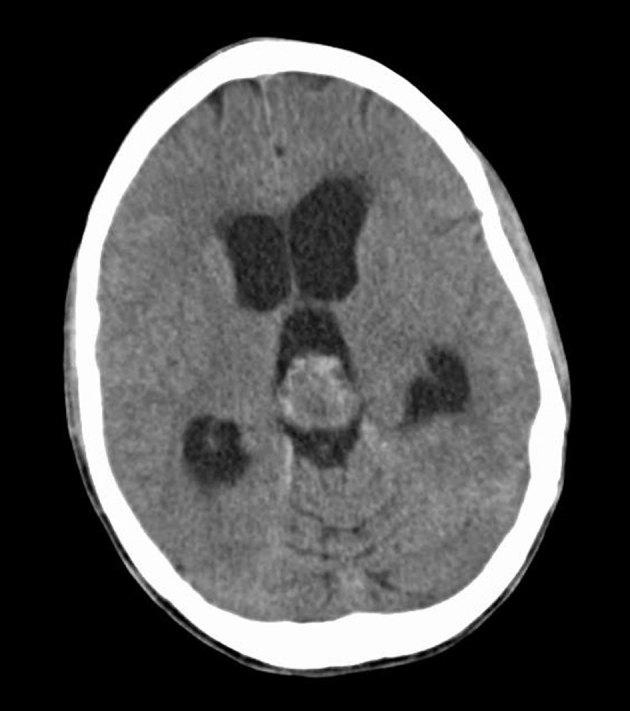

中间分化型松果体实质肿瘤:一种罕见的松果体区肿瘤鉴别诊断。

Pineal parenchymal tumour of intermediate differentiation: a rare differential diagnosis of pineal region tumours.

Pineal parenchymal tumours of intermediate differentiation are a rare type of pineal parenchymal tumours. As indicated by their name, these tumours fall between pineoblastoma (a malignant pineal parenchymal tumour) and pineocytoma (a benign pineal parenchymal tumour). In this article, we present a case of pineal parenchymal tumour of intermediate differentiation that was successfully treated by resection the supracerebellar approach. We also discuss the differential consideration based on epidemiological, pathological and radiological findings.

摘要

中间分化型松果体实质肿瘤是一种罕见的松果体实质肿瘤。顾名思义,这些肿瘤介于松果体母细胞瘤(一种恶性松果体实质肿瘤)和松果体细胞瘤(一种良性松果体实质肿瘤)之间。在本文中,我们报告了一例通过小脑上入路切除成功治疗的中间分化型松果体实质肿瘤病例。我们还根据流行病学、病理学和影像学结果讨论了鉴别诊断。